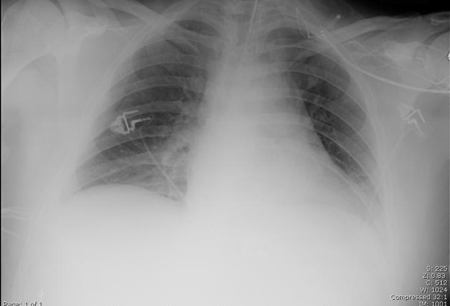

Radiografía de tórax portátil con opacidades bibasales, peor a la derecha que a la izquierda, en un paciente con neumonía adquirida en el hospital

De la colección personal del Dr. F. W. Arnold, División de Enfermedades Infecciosas, Departamento de Medicina, University of Louisville School of Medicine